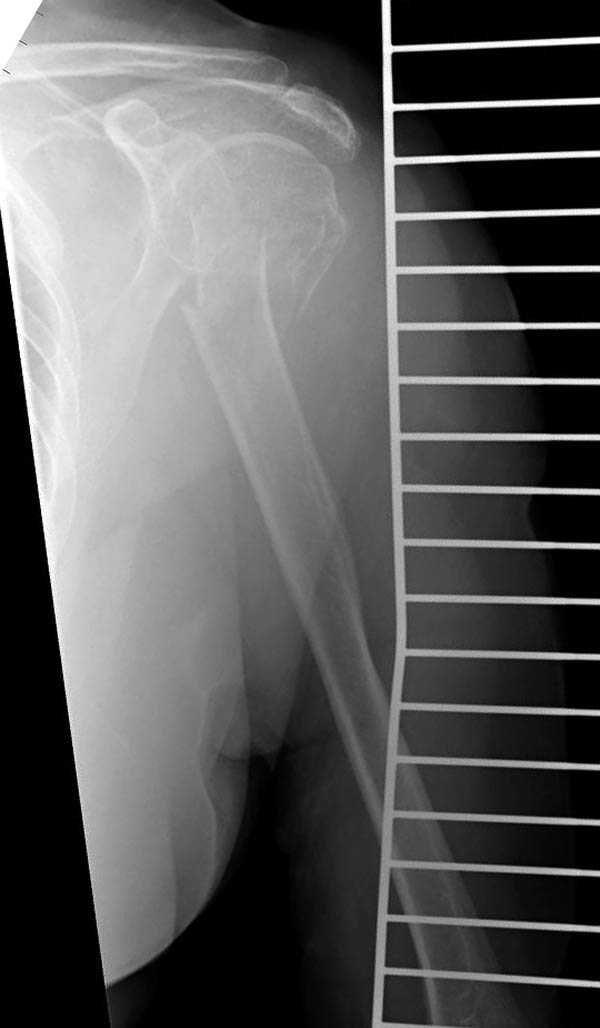

С удовольствием выслушал ваши предложения но все равно сделал по-своему.

Под проводниковой анестезией произвел попытку закрытой репозиции на 10-е сутки, вроде бы неплохо получилось.

Сармиенто доказал, что не только проксимальные переломы плеча, но и переломы длинных костей можно с успехом лечить консервативно. Но, кроме сопоставления перелома, немаловажным фактором является удержание перелома до сращения.

Было бы интересно посмотреть на результат "успешной репозиции" дней через 10?

Извиняюсь за качества снимков, обычный больной в 300 фунтов, портативным ренген аппаратом не пробить.